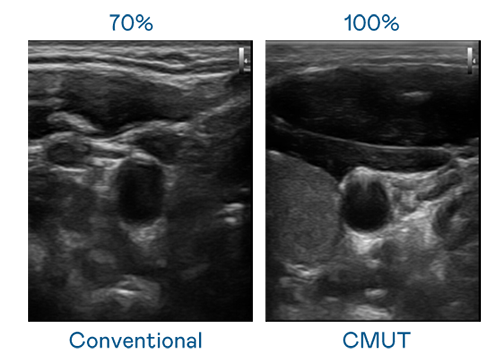

CMUT 技术是一种用电容式微机电元件来产生超音波讯号的技术。与传统 PZT 压电式技术相比,CMUT 频宽增加 30%,更宽频的超音波讯号让影像解析度大幅提升,是实现高影像品质医疗超音波扫描、促进精准医疗发展的关键技术。

大频宽带来超清晰影像

超音波影像的解析度高低,首先取决于探头能发出的讯号频宽。华体汇官网登录入口 CMUT 可提供高清晰的超音波讯号,提供高频宽、高灵敏度、影像纹理细节更高的超音波影像,协助医护人员缩短影像判读时间及利用精准的医疗影像进行诊断。